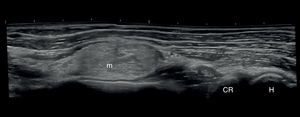

Se realizaron una ecografía de carpo comparativa, que fue rigurosamente normal, y una ecografía del codo y el antebrazo, que mostraba una masa fusiforme de 4,9×1,9cm, sin evidenciarse contacto con estructuras óseas, musculares ni tendinosas (fig. 1). Una RM demostró la presencia de una estructura que rodeaba anteriormente al tendón del bíceps de 5cm en sentido craneocaudal por 1,8 anteroposterior por 1cm en sentido transversal. La lesión presentaba un aumento de intensidad de la señal en las secuencias potenciadas en T1 y en T2, y suprimida en la secuencia de supresión grasa (fig. 2).

Resonancia magnética de antebrazo en T2. Izquierda: aspecto longitudinal donde se observa la masa anterior al radio. Derecha: corte transversal que demuestra la masa provocando un desplazamiento del área teórica por donde discurre el nervio mediano (circulo punteado). c: cúbito; CR: cabeza del radio; H: húmero; m: masa; R: radio.